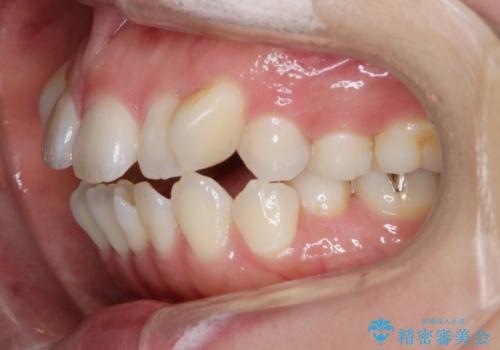

- 前歯のガタつき・噛み合わせの不調を主訴にご来院されました。

患者様のお仕事柄、目立たない装置で矯正したいとのご要望があり、今回はインビザラインを用いて抜歯矯正を行うこととなりました。

本来、抜歯によって得られる大きなスペースのコントロールはワイヤー装置の方が得意とされていますが、こちらの患者様のように犬歯が大きく手前に傾斜していて奥歯の噛み合わせにそれほど問題がないケースではマウスピース装置でも十分にコントロールできることが予測されます。

歯のガタつきの度合いが強い場合や、上下で大きく噛み合わせがズレている時などに、その改善のための大きなスペースを作る代表的手段が「抜歯」です。

一般的には第一小臼歯(犬歯の一つ隣の歯)を抜くことが多く、前歯のガタつきを改善したり口元を引っ込める場合に利用されます。